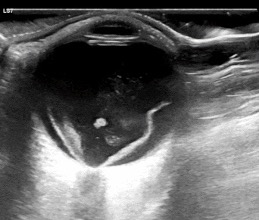

Each cardiac view offers a different perspective of the LV, displaying various walls and myocardial segments. The LV is typically divided into three levels: basal, mid, and apical. The basal segments are located closest to the atrioventricular valves and represent the upper portion of the LV; the mid segments are situated in the middle, at or around the level of the papillary muscles, and the apical segments are near the apex of the ventricle. Understanding which walls are visualized in each view is key to assessing LVfx.

Figure 1ab: LV levels in the PLAX view (a) and A4C (b) in cardiology convention